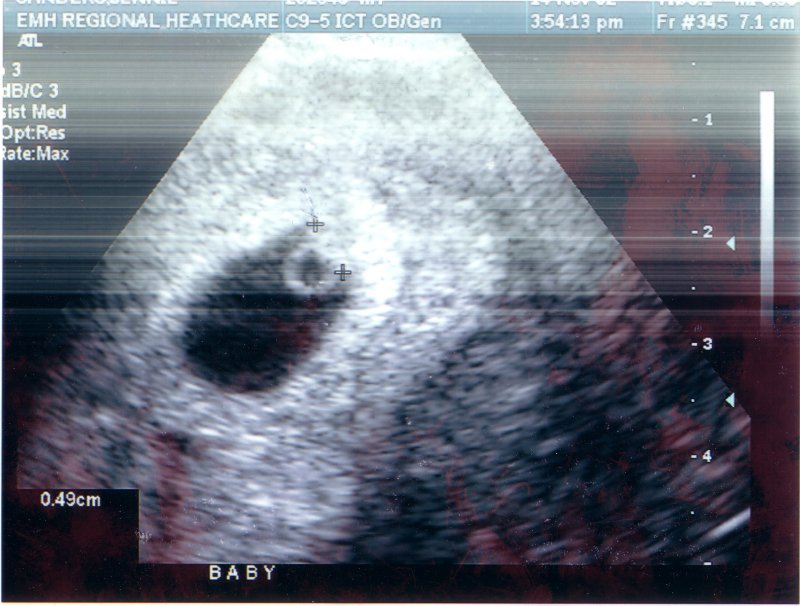

A first look at little Ben. He's about the size of a grain of rice in this picture.

November 14th, 2002